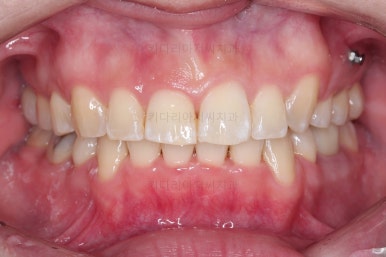

초진 시 입안의 모습입니다.

전반적으로 치열이 삐뚤고, 특정 앞니는 톡 튀어나가 미적으로 좋지 못한 상황이었습니다.

이갈이, 이악물기 습관도 있어서 앞니는 삐뚤어진 채로 치아가 많이 갈려있는 상황이었습니다.